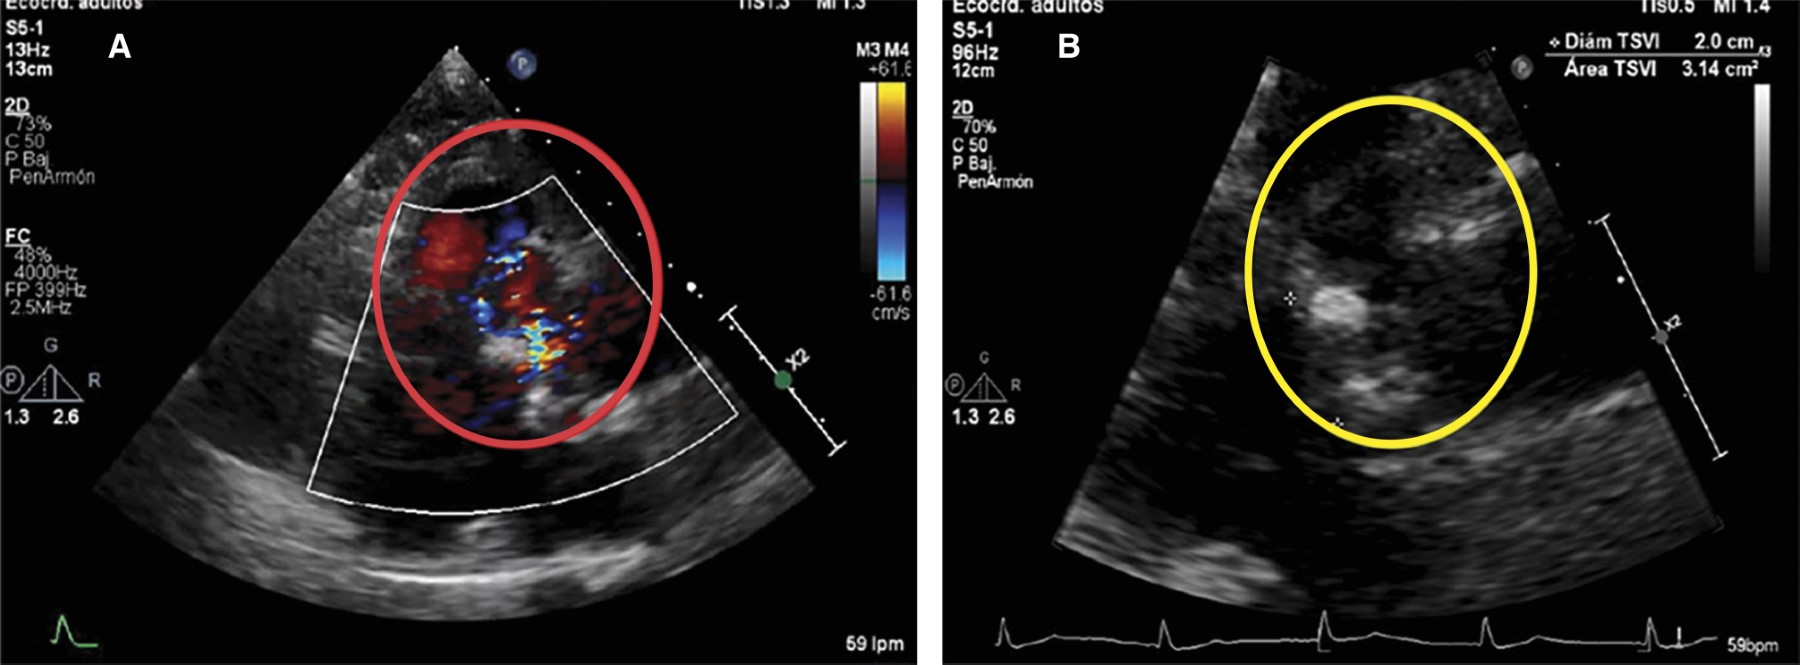

Figura 1